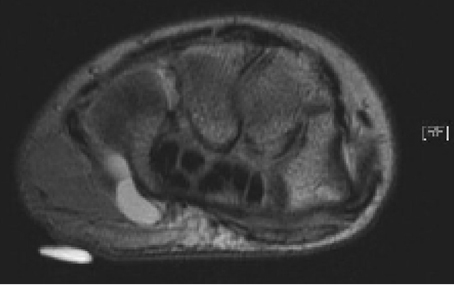

Ulnar tunnel syndrome has been well-described in the literature and might be the result of various causes, including ganglia 8 , 9 , 10 , 11 (as depicted in ► Fig. 26.4), fractures or dislocations of the ulnar side of the wrist, 9 , 12 , 13 anomalous muscle bellies or fibrous bands, 11 , 14 , 15 (as shown in ► Fig. 26.5), hemangiomas, 16 bipartite hamate, 17 giant cell tumors, 18 thrombosis of the ulnar artery, 9 , 11 , 19 osteoarthritis of the distal radioulnar joint and carpal joints, 20 , 21 rheumatoid tenosynovitis, 22 other benign soft tissue masses (shown in ► Fig. 26.6), bicycle racing, and other activities that require either prolonged wrist hyperextension or continuous pressure on the hypothenar eminence. 16 More recently, with the extreme popularity of indoor cycling classes, we have seen an increased prevalence of this condition which is termed cyclers’ palsy.